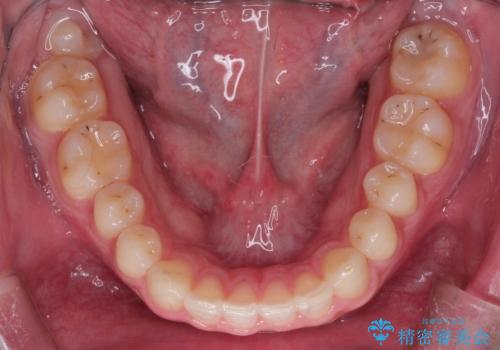

初診時の歯並びの状態としては、上下ともに前歯部の中等度のがたつきがあり、前歯には正中離開があり過蓋咬合を呈してい状態でした。

また奥歯の噛み合わせのズレもあり、特に左は顕著に認められました。

検査の結果、抜歯なし/ワイヤー矯正にて治療を行いました。

また、成長期終盤の男の子だったため成長の余力(下顎を前に牽引んし成長を促進する)を期待しアドバンシンクという装置を使い、下顎の骨の成長を利用した矯正治療を行いました。